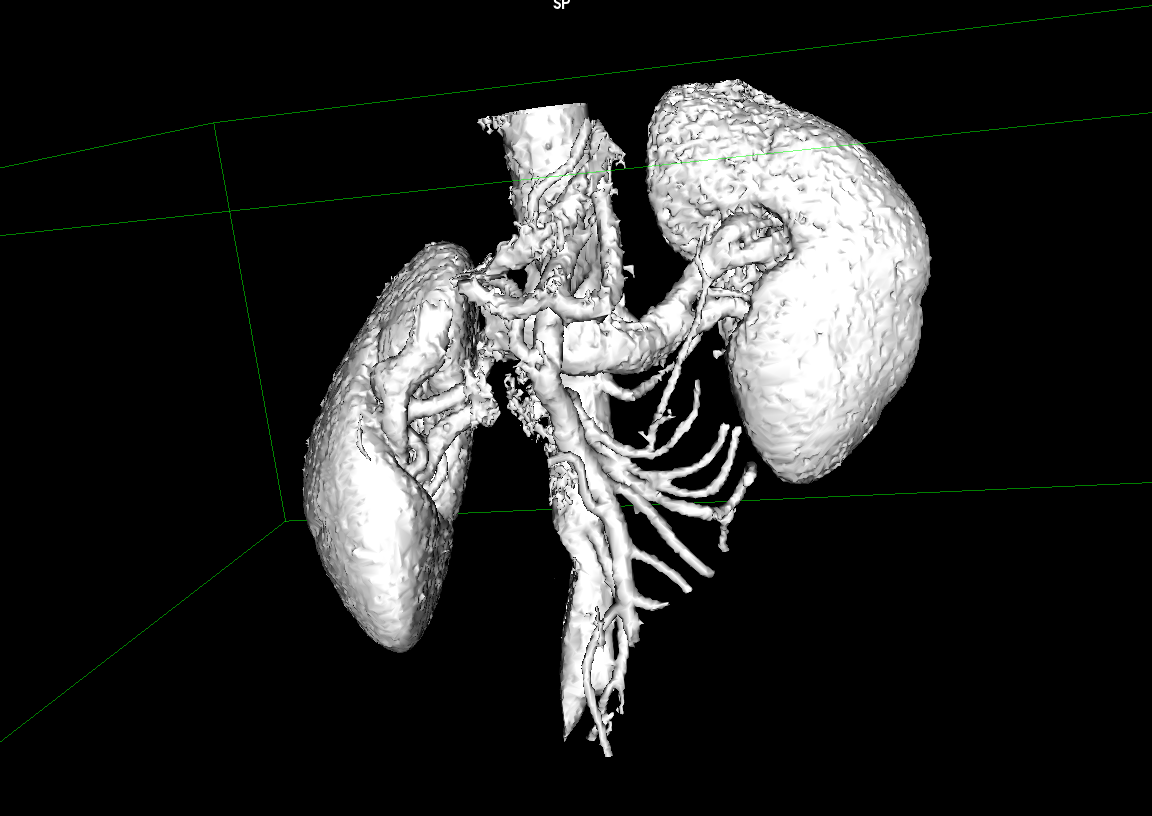

Kidney CT Data

Extracted Mesh

Extracting Data

This 3D Kidney model was built using raw data from a CT Scan. The first step is to segment the kidneys from the rest of the scan to create a base mesh of the anatomy.